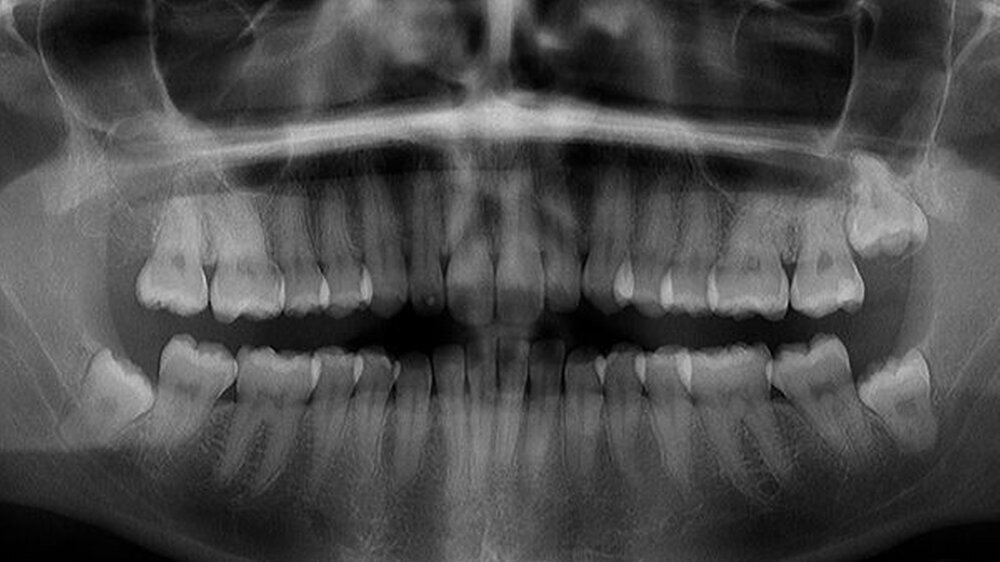

Nach erfolgtem Eingriff unter stationären Bedingungen konnte die Nachbehandlung ambulant in unserer Praxis erfolgen und gestaltete sich im wesentlichen störungfrei. Die Röntgenkontrolle nach vier Jahren zeigte operationsbezogen einen Normalbefund (Abbildung 4): Kieferhöhlen rechts und links (soweit beurteilbar) lufthell, Zähne 28, 38, 48 in etwa orthograd (also: Verlaufsbeobachtung vertretbar).

Die anderen Zähne im I. Quadranten blieben vital, die infraorbitale Sensibilität hatte sich innerhalb kurzer Zeit (Wochen) normalisiert, die Doppelbilder waren verschwunden. Die Patientin äußerte sich im weiteren Verlauf sehr zufrieden über Diagnostik und Therapie. Sie hatte auch keine Beschwerden mehr verspürt. Die Zähne 28, 38, 48 wollte die Patientin bis heute nicht entfernen lassen.